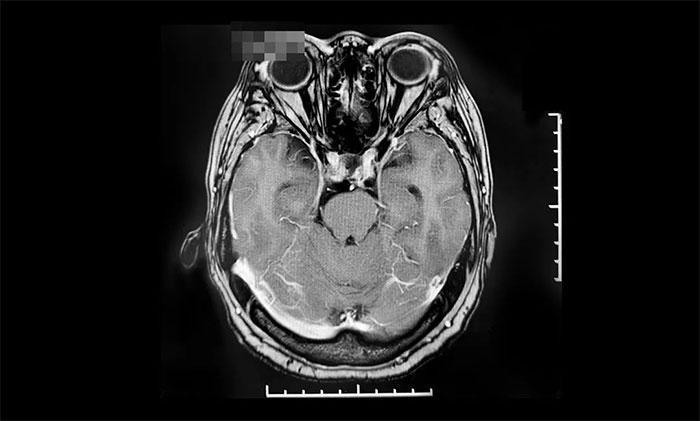

▲ 出院14個(gè)月后復(fù)查影像

2022年8月,因視力下降就醫(yī),復(fù)查提示腫瘤復(fù)發(fā),遂來(lái)上海藍(lán)十字腦科醫(yī)院進(jìn)行伽瑪?shù)吨委,后順利出院。今?0月,患者來(lái)院復(fù)查,影像學(xué)檢查提示腫瘤體積較治療前明顯縮小,患者視力較前改善,控制良好,陳琦主任叮囑其繼續(xù)隨訪觀察。